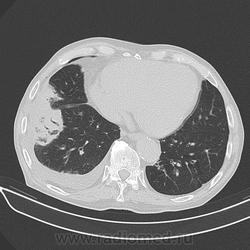

Мужчина 72 лет, лежит в кардиологии с ИБС.

Температуры нет, ОАК - Le - 10, сдвига формулы нет;  кашель редкий не продуктивный, иногда С ПРОЖИЛКАМИ КРОВИ.  Слабость, одышка.

Спустя несколько дней провели КТ  "для исключения онко-патологии".

p.s.  обратите внимание на зону аналогичного уплотнения в левом легком (видно на аксиалах).

Дайкомов не вижу, по джипегам расценил бы как ТЭЛА с субсегментарными инфарктами легких, достаточно характерная, как-бы "всепененная" структура.

,.. и гидротораксом справа, и (осумкованным/ограниченным-?) пневмотораксом (в переднем отделе, параперикардиально, опять же, справа)... Или пневмоперитонеум туда добрался... по неисповедимым своим путям?

я за центральный рак правого легкого

я думаю пневмоторакс может быть последствием "криво" выполненной плевральной пункции.

по моему есть узел в правом корне, н/долевого